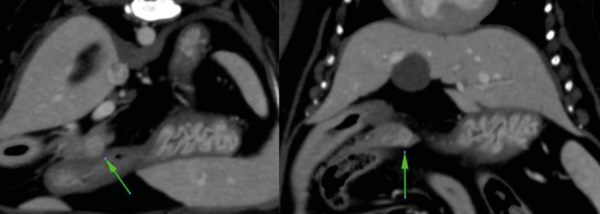

En casos de obstrucción biliar se debe considerar la duodenotomía y la colocación de un stent temporal en el colédoco, que sale al duodeno a través de la papila duonedal mayor, mientras se resuelve la compresión temporal por el absceso/inflamación (imágenes 2A y 2B). La colocación de stents de colédoco también se ha descrito en gatos.25-27 En esta especie, durante este procedimiento se debe tener cuidado de no cateterizar el conducto pancreático debido a la conexión anatómica entre el conducto pancreático y el conducto biliar común.28